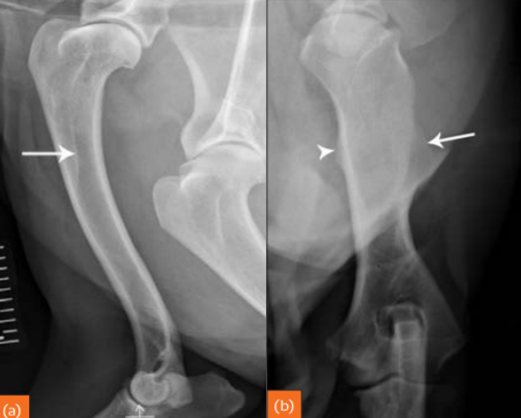

Fractures can be either..

primary or secondary.

Also, complete or incomplete. (periosteum can be intact with fracture line otherwise).

Left image: gunshot caused fracture.

Right image: osteosarcoma caused fracture.